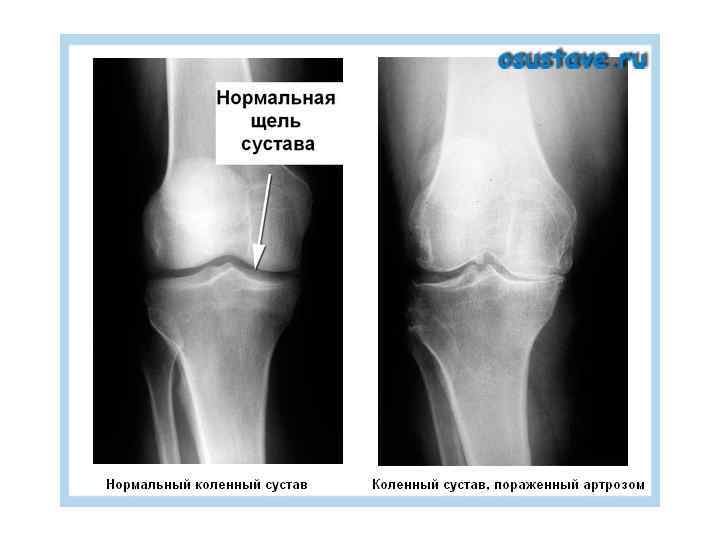

ЛУЧЕВАЯ ТЕРАПИЯ НЕОПУХОЛЕВЫХ ЗАБОЛЕВАНИЙ ПОКАЗАНИЯ: • 1. Воспалительные заболевания кожи, ПЖК, желез хирургического профиля: фурункулы, карбункулы, абсцесс, флегмона, гидроаденит, рожа, панариций, мастит, тромбофлебит, парапроктит… • 2. П/операционные осложнения: анастомозит, фантомные боли, свищи, остеомиелит • 3. Дегенеративно-дистрофические заболевания КСА: деформирующий артроз, оссифицирующий бурсит, плече-лопаточный периартрит, пяточные шпоры и т. д. • 4. Воспалительные и гиперпластические заболевания нервной системы: сирингомиелия, неврит, радикулит, невралгия, плексит • 5. Заболевания кожи: нейродермит, зудящие дерматозы, грибковое поражение волос головы